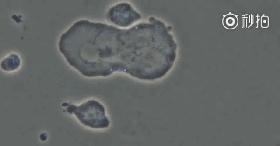

2、队伍中的一名勇士找到了突破口,癌细胞瞬间瓦解,兄弟部队群起而攻之。

图片

3、癌细胞已经毫无抵抗之力,逐渐被消灭,NK细胞顺利完成任务。